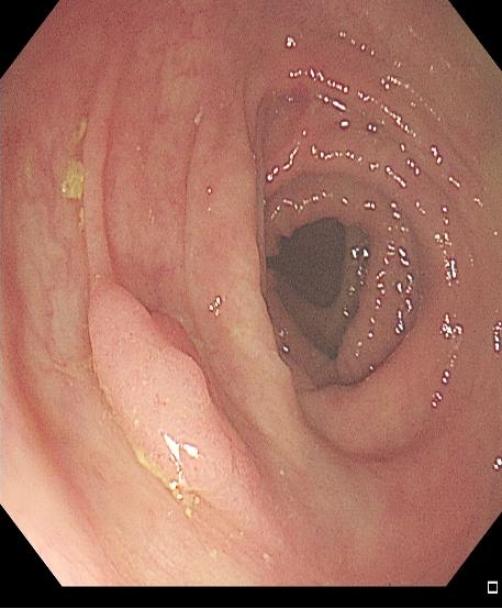

操作过程中应夹住息肉头端,适当上提(可避免损伤肌层),与肠壁保持适当距离,当息肉蒂部出现发白时,停止电凝,钳除病变。应注意是,切除息肉不易过大,否则会造成通电时间延长,增加全层损伤的风险(图1)。

图1 热活检钳除术示意图,A 钳除前,B 钳除后创面。C-D:热活检钳除术注意事项,息肉体积过大,增加电凝时间,造成透壁性损伤。2